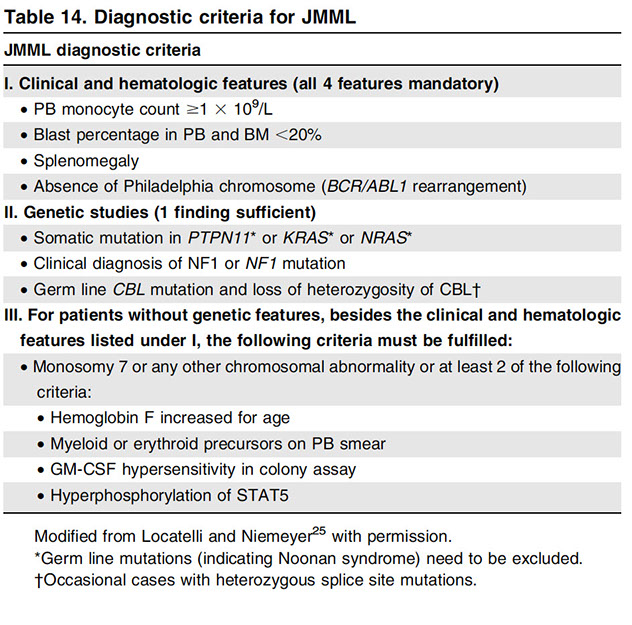

Juvenile MyeloMonocytic Leukemia (JMML)

Childhood disorder (male predominance) with granulocytic and monocytic proliferation with low blast counts and characteristic RAS/MAPK mutations, usually minimal dysplasia

- assoc c NF1 (10-20% of cases; thus not a criterion)

- kids c Noonan syndrome get a JMML-like dz that resolves spontaneously

- Blasts + Promonos <20% in PB and BM

Present c S-megaly, enlarged tonsils, B symtoms, inc HgF, can have skin and spleen infiltrates

Diagnostic criteria:

I. Clinical + hematologic features (need all 4)

1.) Monocytosis in PB

2.) (Blasts + promyelocytes) <20% in PB and BM; (will never see Auer rods)

3) Splenomegaly

4.) No Ph chr or BCR-ABL1 fusion gene

II. Genetic findings (1 sufficient)

- Somatic PTPN11 or KRAS or NRAS

- Clinical diagnosis of NF or NF mutation

- Germline CBL mutation and LOH of CBL

III For pts w/o genetic features, besides the clinical and hematologic features under I, must have:

- monosomy 7 or any other chromosomal abnormality, or at least 2 of the following:

- Inc HbF; Immature granulocytes in PB; GM-CSF hypersensitivity of myeloid progenitor cells in vitro; hyperphosphorylation of STAT5

PB is most important in dx'ing; see anemia, inc leukos and Tbcpenia

~65% have normal karyotype, ~25% monosomy 7

- BCR/ABL1 negative

- RAS and MAPK pathway mutations are characteristic

- PTPN11 gene mutations, SHP-2 phosphatase

- RAS gene mutations

- NF1 gene inactivation

Increased cellular sensitivity to GM-CSF

Hematopoietic stem cell transplantation

Monosomy 7 in 25%; 65% have normal karyotype

DDx: Leukemoid reaction, CML (can occur in kiddos, but very rare), kids c Noonan syndrome have PTPN11 mutation encoding SHP2 or in KRAS

Px: Rapidly fatal if left untreated

- need stem cell transplant or die in 1 year

-- rarely transforms to AML